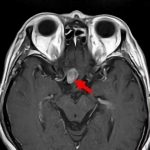

'14年6月

40代

海綿状血管腫

No.’14_104 手術前1

No.’14_104 摘出 前

No.’14_104 摘出 後